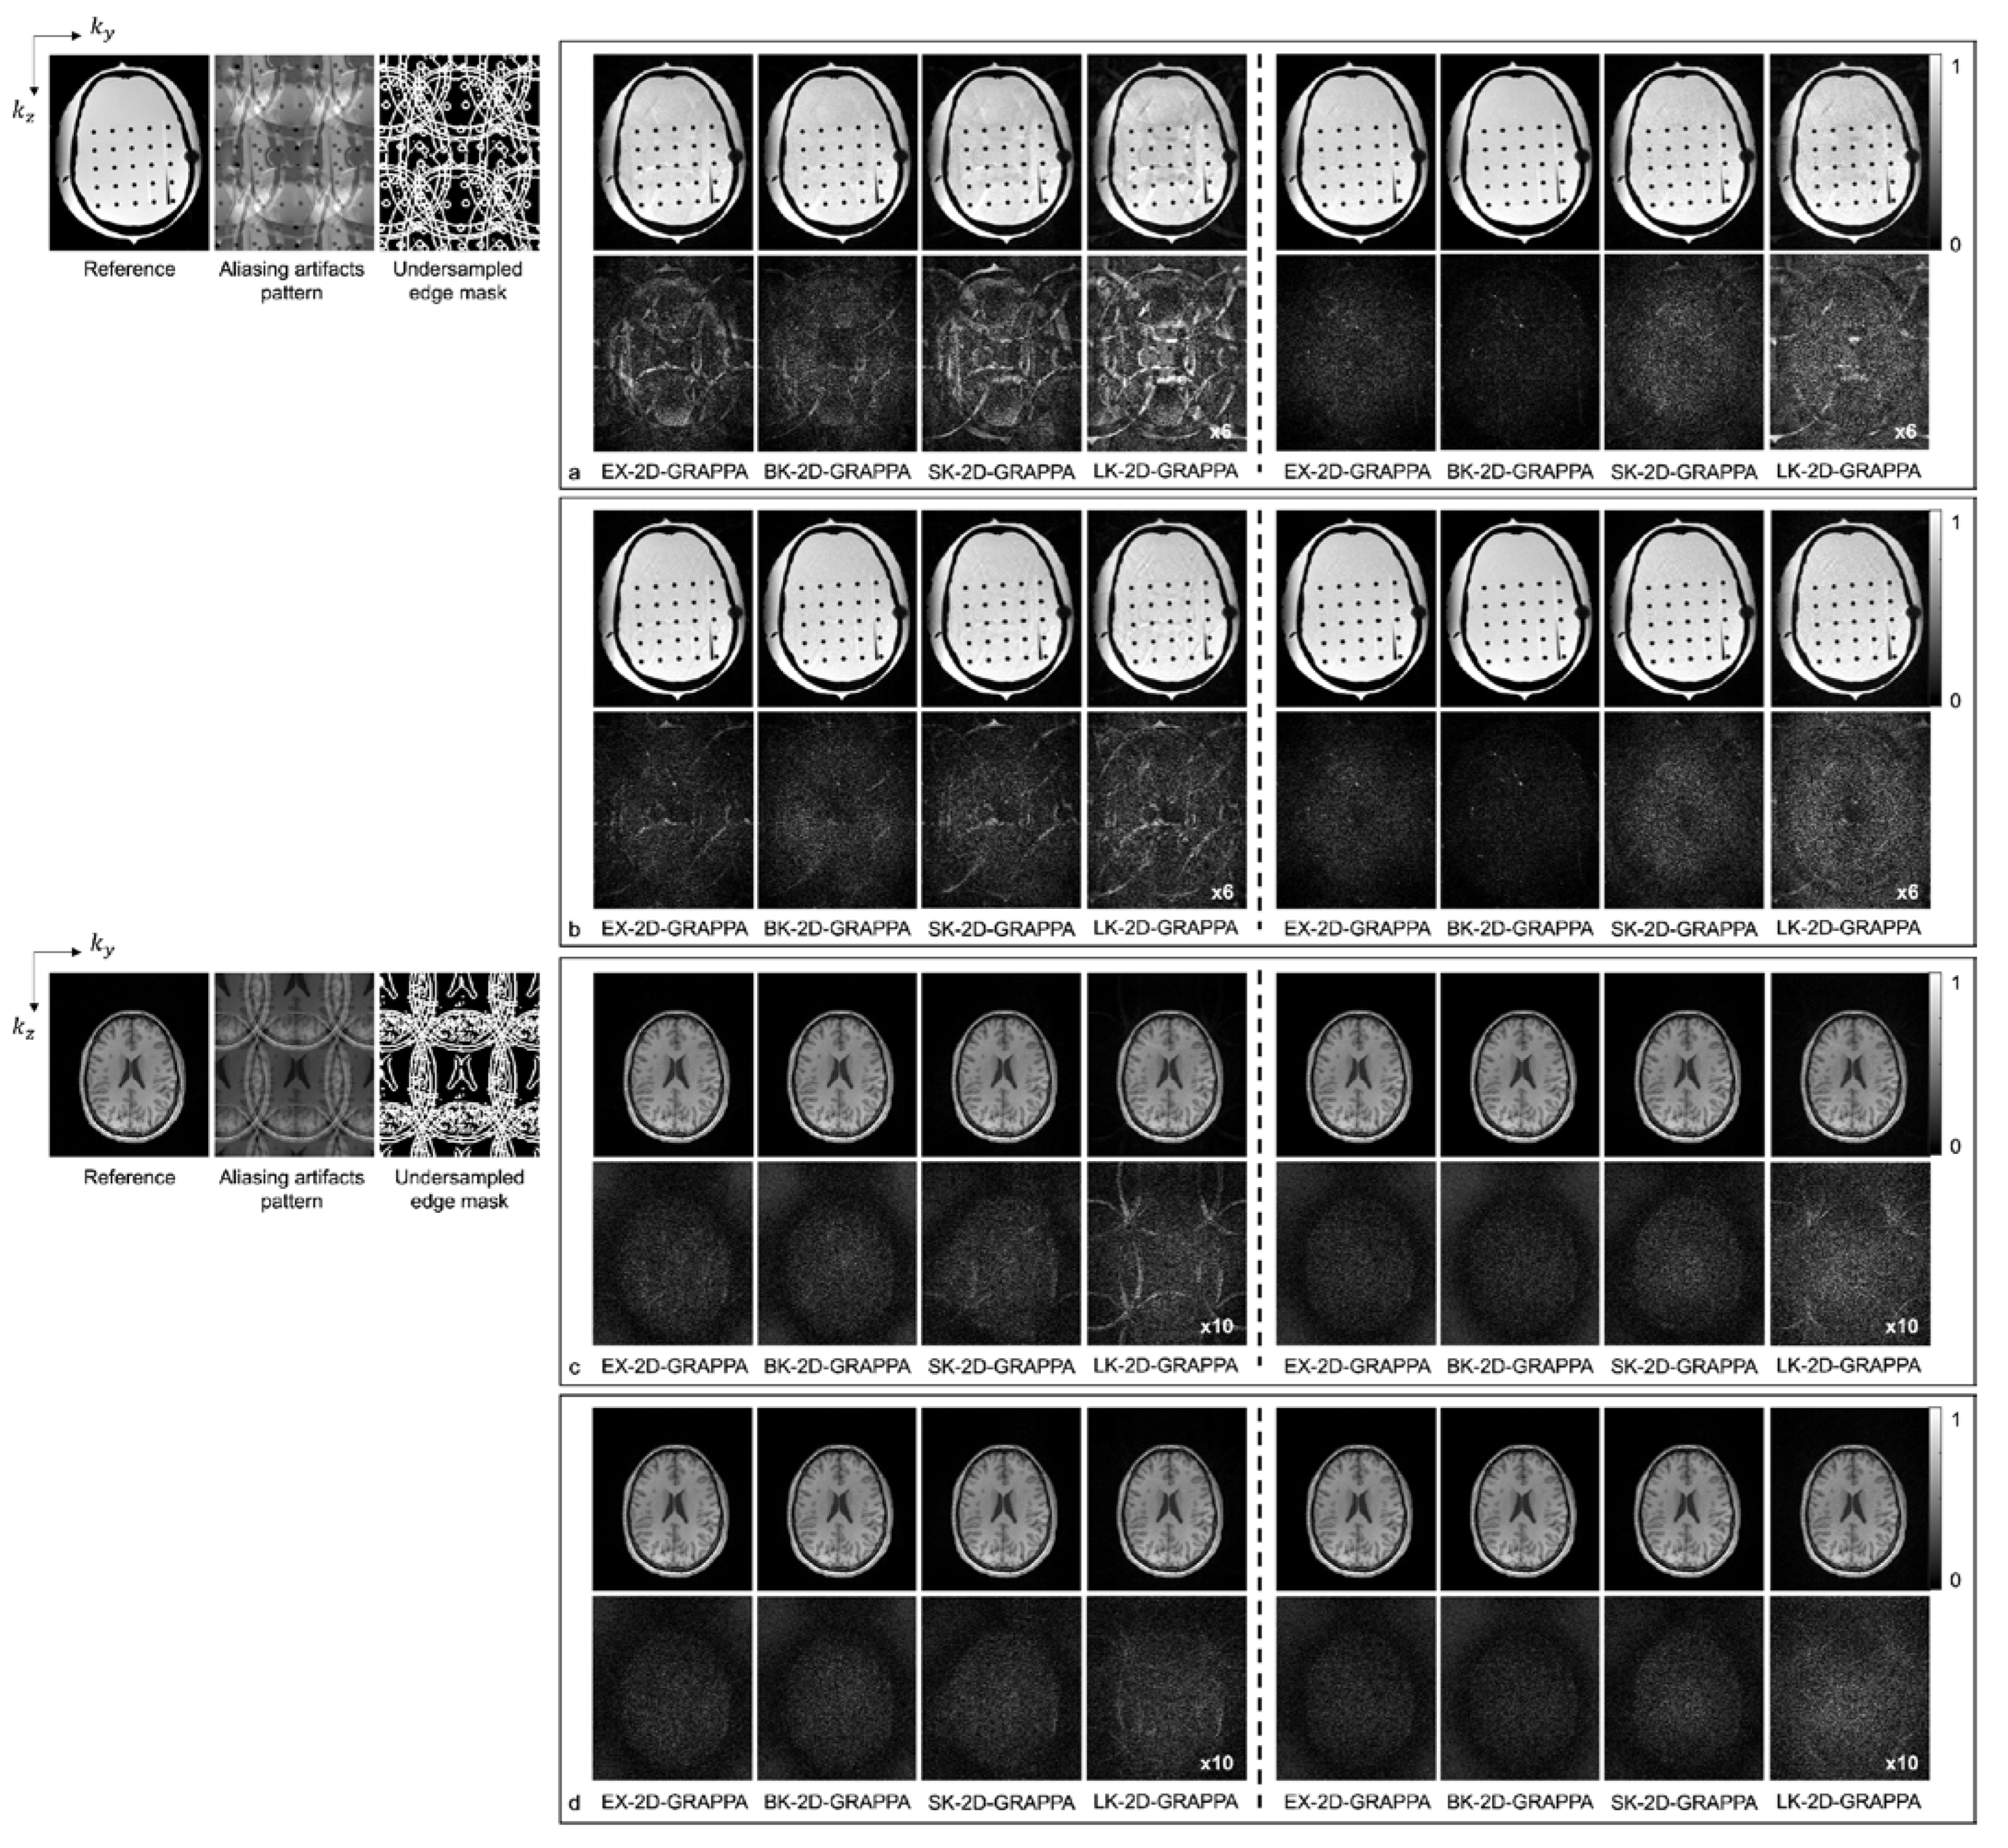

Figure 6 shows images reconstructed from the acquired phantom (a,b) and human brain (c,d) data. The reference image reconstructed from fully sampled k-space data, an image showing the pattern of aliasing artifacts and an undersampled edge mask are also presented on the left. The missing k-space data were estimated from acquired data with 24 × 24 k-space reference lines to generate the final images, and the difference images were also calculated by subtracting the reconstructed images from the reference image. In Figure 6a,c, the images show the reconstruction results obtained when the k-space reference lines were excluded before reconstruction. On the other hand, Figure 6b,d shows images obtained when the reference lines were included for reconstruction. Images from the first to the fourth columns were reconstructed with the basis kernels, and images from the fifth to eighth columns were reconstructed with the expanded kernels using the 2D-GRAPPA algorithms named below. In the reconstructed images of the acquired phantom data, the BK-2D-GRAPPA algorithm eliminated more aliasing artifacts than other 2D-GRAPPA algorithms. It was difficult to visually observe significant differences between different algorithms except for the LK-2D-GRAPPA algorithm, which showed severe artifacts in the reconstructed images of in vivo data. Nevertheless, the BK-2D-GRAPPA algorithm showed fewer errors when compared with the reference image than other 2D-GRAPPA algorithms.

Figure 6.

The reconstructed images of acquired anthropomorphic skull phantom (a,b) and human brain (c,d) data with 24 × 24 k-space reference lines and AF = 4 (2 × 2). The k-space reference lines were (a,c) excluded and (b,d) included at the end of the reconstruction. Columns 1–4: basis kernel. Columns 5–8: expanded kernel.

Figure 8 shows the reconstructed images of the acquired (a,b) phantom and (c,d) human brain data, where asymmetric acceleration factors were used. For (a) and (c), the kz direction was more accelerated (i.e., Ry × Rz = 2 × 4), and for (b) and (d), the ky direction was more accelerated (i.e., Ry × Rz = 4 × 2). In addition to the reconstructed images, a reference image with fully sampled k-space data, an image displaying the pattern of aliasing artifacts and an undersampled edge mask are presented on the left. In Figure 8a–d, the top rows display the reconstructed images using 32 × 32 k-space reference lines, and the bottom rows show the difference images between the complex-valued reference and the reconstructed images. As with the computer simulation, images in columns 1–4 and 5–8 were reconstructed using the basis kernels and the expanded kernels, respectively.

As demonstrated by Figure 5, Figure 6, Figure 7 and Figure 8, the number of aliasing artifacts increased as the total AF increased from 4 to 8. In general, the images reconstructed by the BK-2D-GRAPPA algorithm showed the smallest difference from the reference image in the noise-free (Figure 7a,b) and the noise-added (SNR = 30 dB) simulation data (Figure 7c,d). In addition, the quality of the reconstructed image was improved when the expanded kernel size was utilized. As shown in Figure 8, the BK-2D-GRAPPA algorithm also showed the smallest number of aliasing artifacts in the phantom and in vivo data, regardless of which direction was more accelerated. The number of residual aliasing artifacts also decreased with the expanded kernel size.